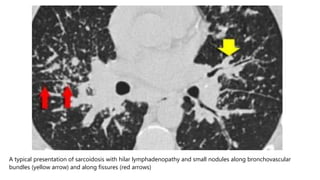

A typical presentation of sarcoidosis with hilar lymphadenopathy and small nodules along bronchovascular

bundles (yellow arrow) and along fissures (red arrows)

 Small nodules in a perilymphatic distribution (i.e. along subpleural

surface and fissures, along interlobular septa and the

peribronchovascular bundle).

 Upper and middle zone predominance.

 Lymphadenopathy in left hilus, right hilus and paratracheal. Often

with calcifications.